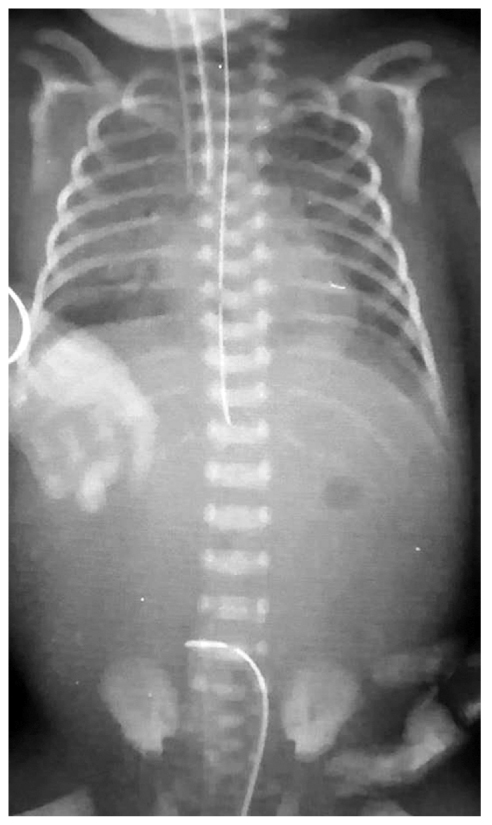

Рис. 4. Обзорная рентгенография органов грудной и брюшной полости: желудочный зонд расположен под диафрагмой вне желудка

Fig. 4. Plain thoracic and abdominal radiography: nasogastric tube tip is located beneath the diaphragm, without the stomach